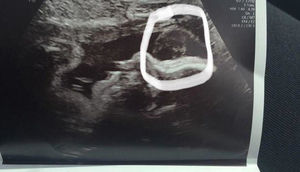

Körpəsinin ultrasəs müayinəsində ölən nənəsini görən qadın dəhşətə gəldi - FOTOLAR